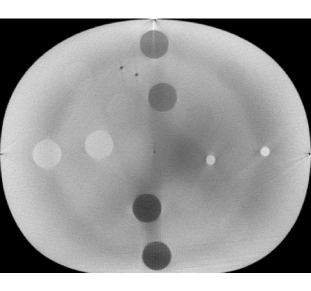

where is the current value of the parameter, is the Metropolis-Hastings (M-H) proposal, is the sufficient statistic of the Potts model, and is the expectation with respect to the distribution of given . The value of this definite integral can be approximated by simulating from the MRF defined by Eq. (1) for fixed values of and then interpolating between them. We used the Swendsen-Wang algorithm for simulating from , as explained in Section 3.3. Fig. 2 illustrates linear interpolation of on a 3D lattice for and ranging from 0 to 2 in increments of 0.1.

The value of the inverse temperature obtained by path sampling also changed as the uncertainty in the prior increased. Fig. 5 shows the posterior mean of for the 27 cone-beam CT scans. It is evident from Eq. (4) that is a free parameter that balances the strength of spatial association against the external field (which in our model is data prior). The external field prior becomes weaker as the standard deviation increases, thus the value of is lower to compensate.